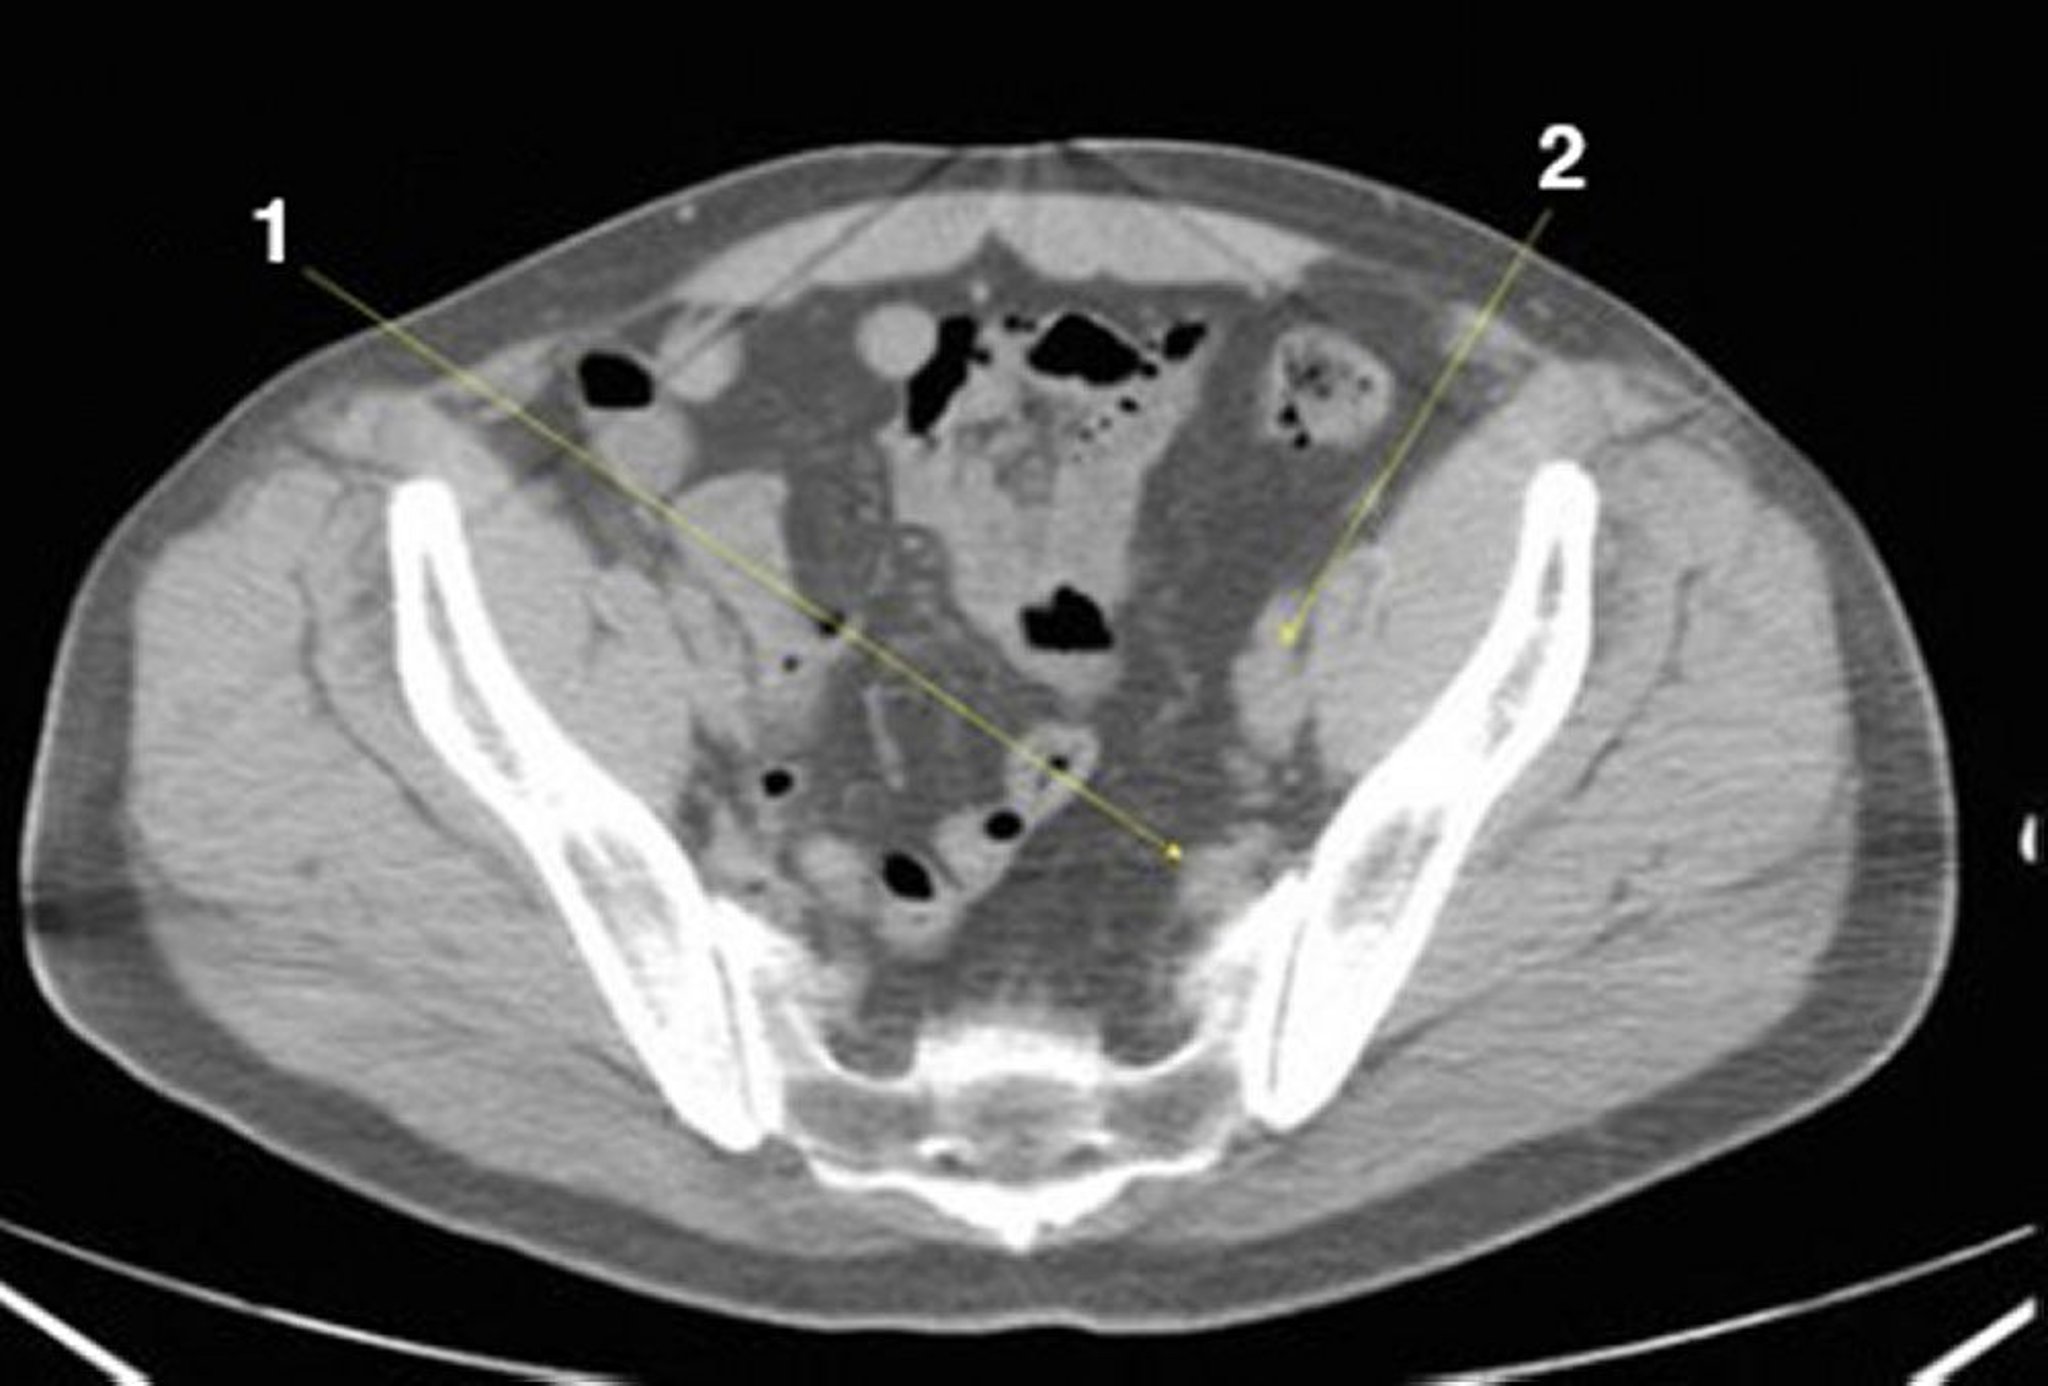

TC senza contrasto dell'addome e della pelvi che mostra un'anatomia normale (Slide 24)

1 = vasi iliaci interni; 2 = vasi iliaci esterni.